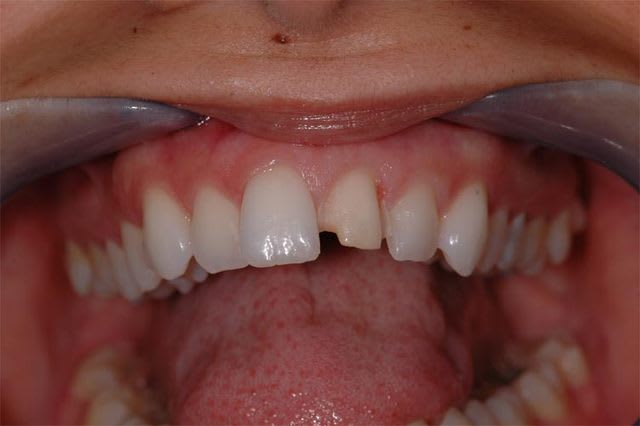

Pour info puisqu'on a abordé l'ortho....

Quid de la mandibule? Elle serait pas en classe II avec une supra cette patiente? Quid aussi de son occlusion?

Je sais je suis un emmerdeur mais bon... perso non seulement j'essaie de pratiquer le tact et mesure (dur dur quand y'a pas de "mesure" avec mes CMU...)mais j'essaie aussi de répondre à des demandes non formulées comme par exemple remettre cette bouche en état (le probléme de l'alignement des collets et de la forme de la dent étant un des éléments à traiter).

Tu lui a fait "les bras" à cette petite? Pense à le faire quand tu régleras finement son occlusion aprés la pose de sa facette.